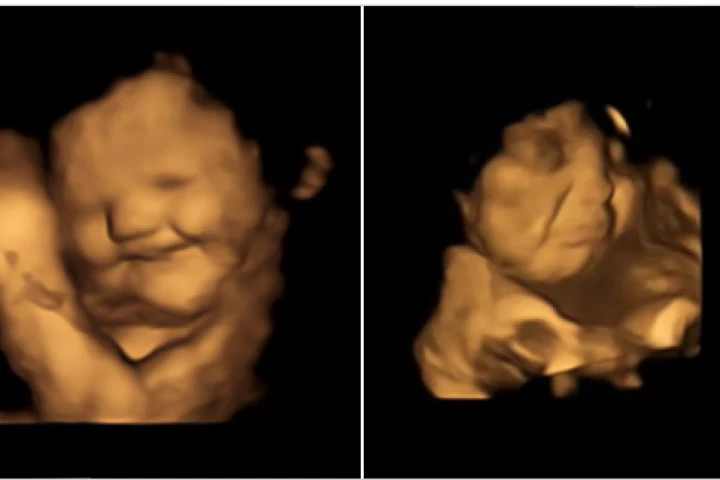

An extraordinary study has recorded the first evidence of babies in the womb reacting to flavors of foods, showing fetuses crumpling up their faces in disgust after a mother consumes kale or smiling with glee in the presence of carrot flavors.